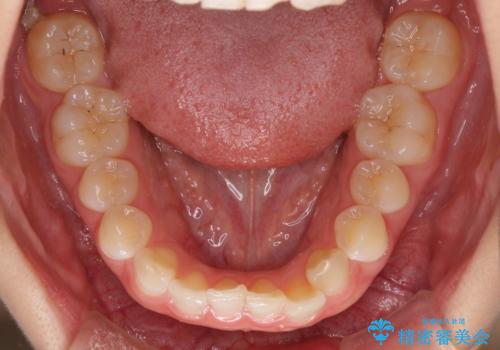

- 1年後に海外に転居するため、気になる前歯を矯正治療で整えたいとのことで来院された患者様です。

下顎は叢生が強かったため、奥歯までワイヤーを装着し、上顎は前歯の一部のみ気になっていたので、その部分にだけワイヤー装置を装着することとしました。